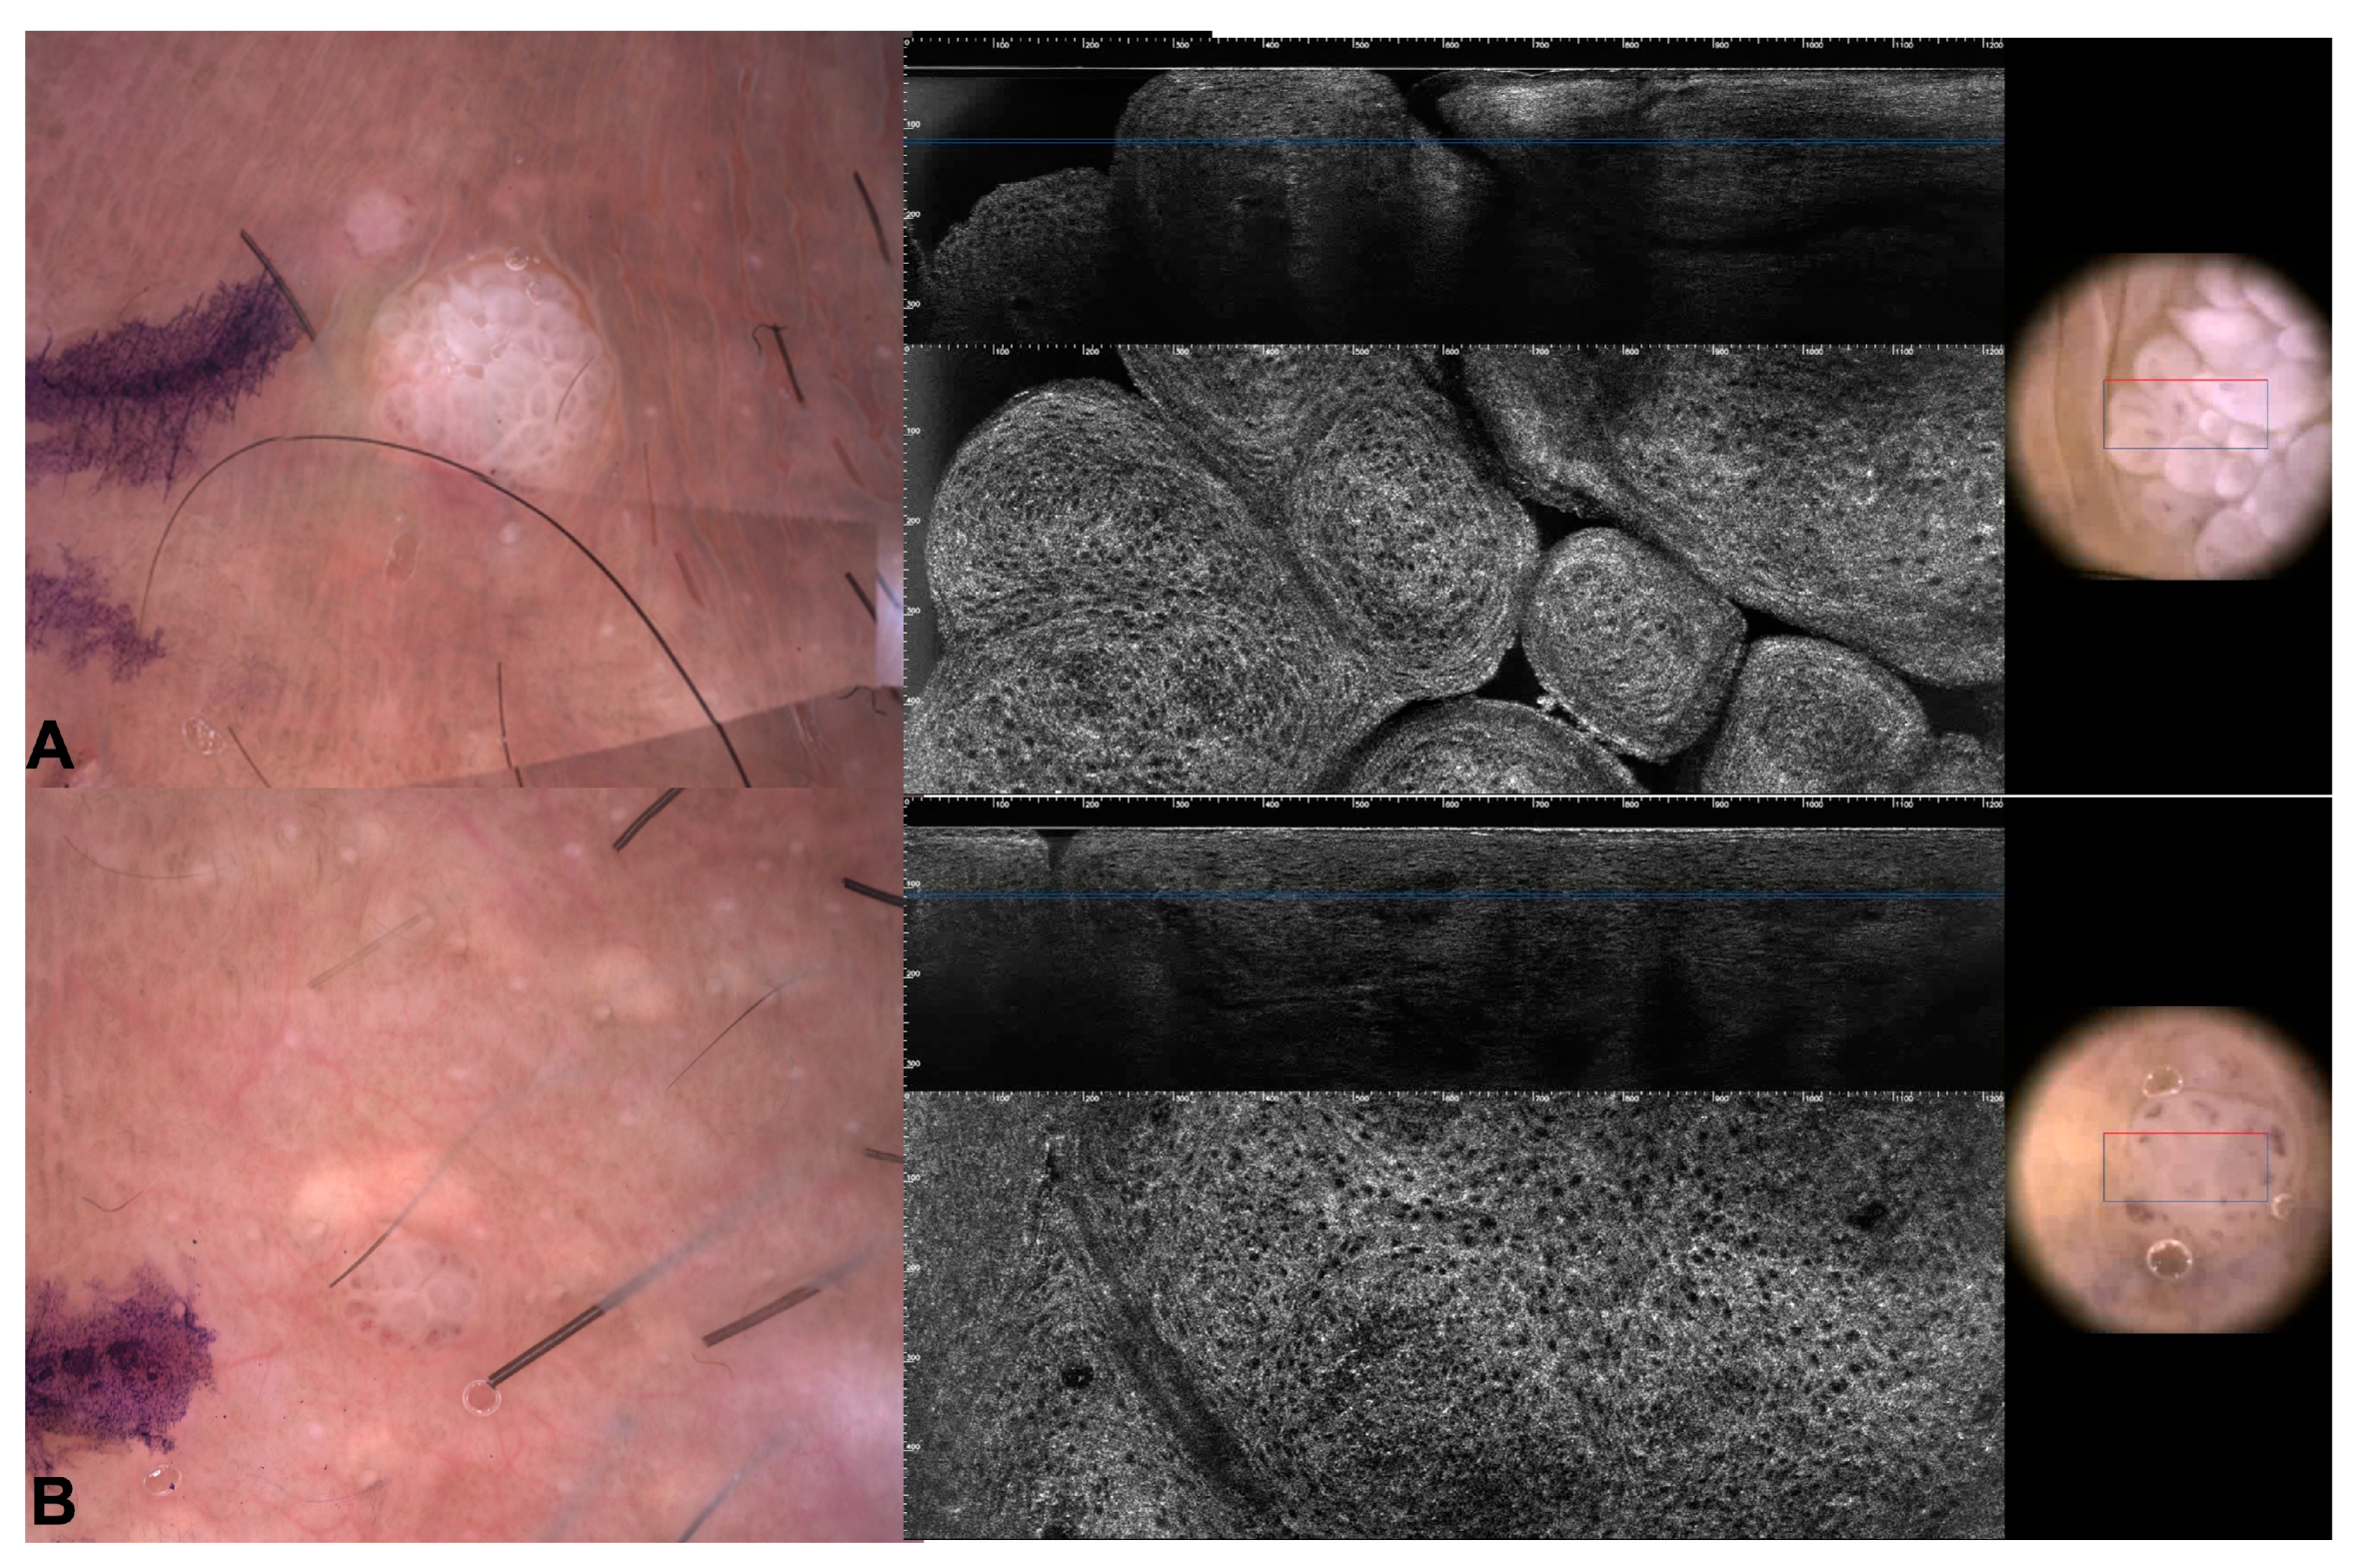

3.1. Images of the Genital Warts

3.2. Images of the Imitators of Genital Warts